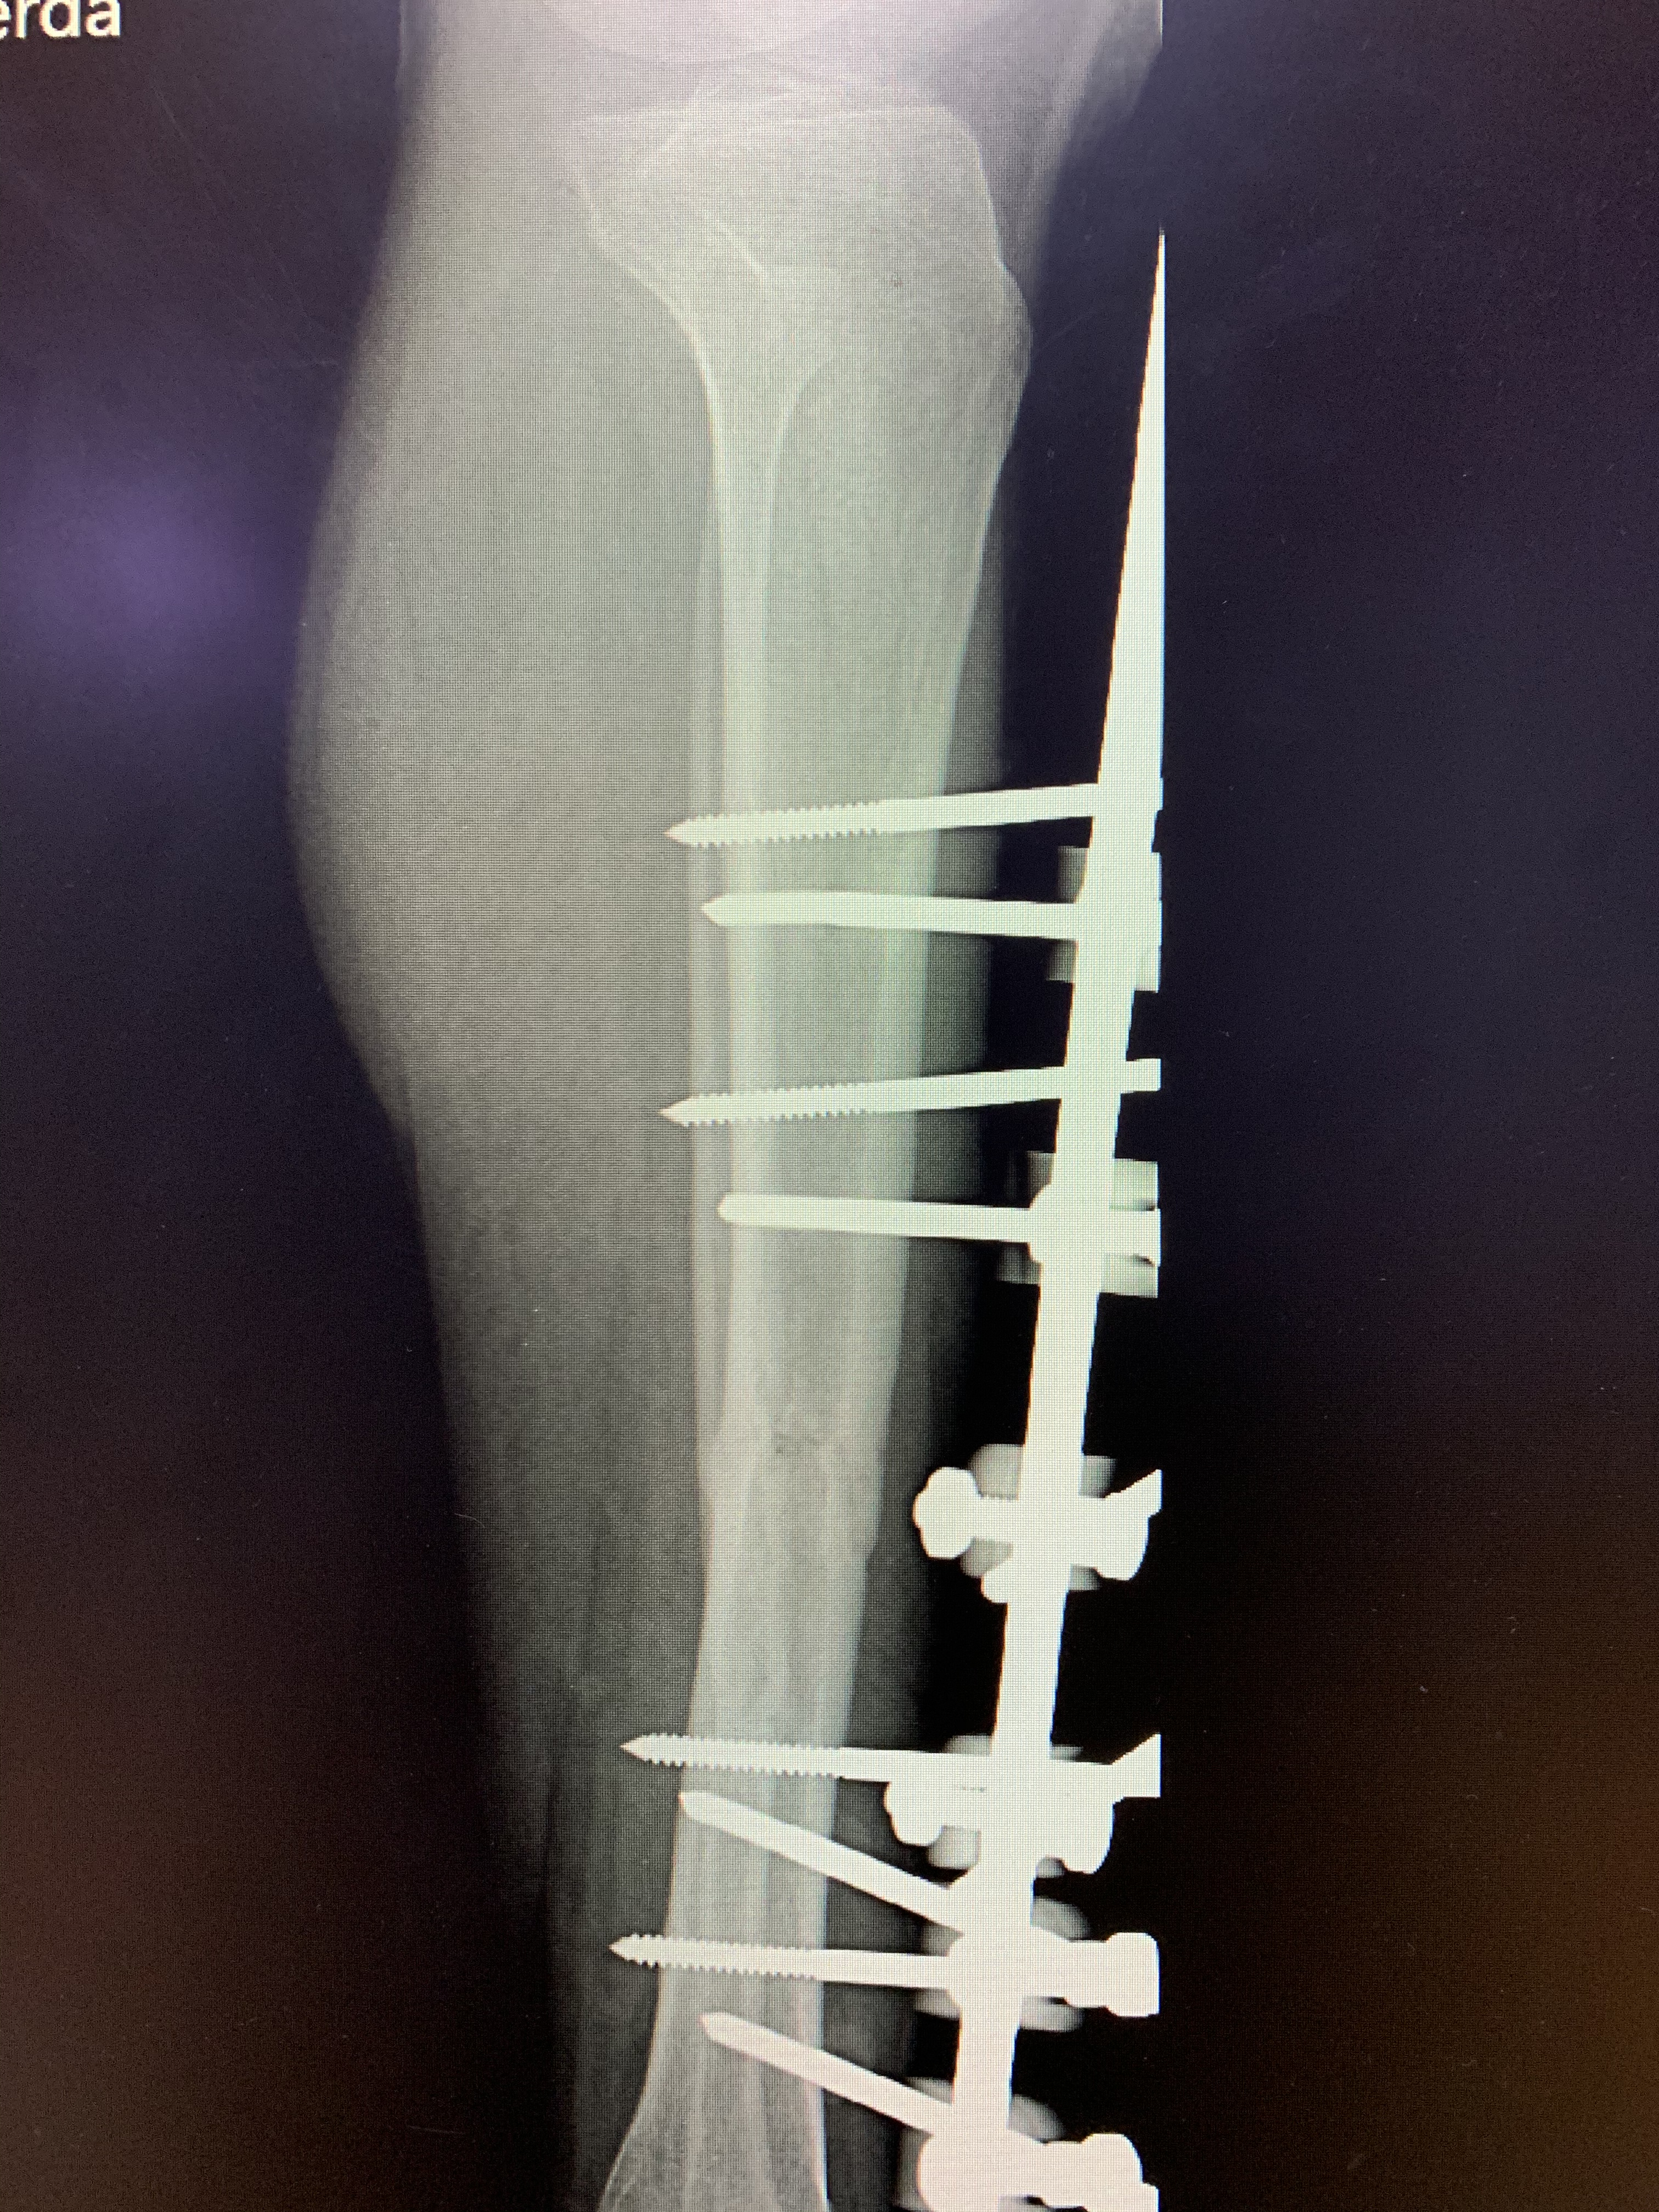

Galería de fotos clínica, servicios, cirugías, casos de pacientes Visítenos, ambiente limpio, agradable y seguro. Trabajando Operando en tiempos de coronavirus Dr Barquero Traumatologo Compartir en X (Se abre en una ventana nueva) X Comparte en Facebook (Se abre en una ventana nueva) Facebook Imprimir (Se abre en una ventana nueva) Imprimir Compartir en WhatsApp (Se abre en una ventana nueva) WhatsApp Enviar un enlace a un amigo por correo electrónico (Se abre en una ventana nueva) Correo electrónico Me gusta Cargando...